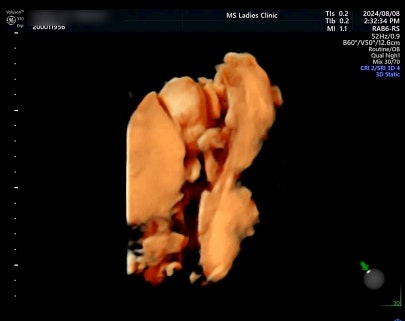

31주 정기검진 귀여운 용접이? 오늘은 얼굴도 나름 보여주고 벌써 볼살도 생겨짜나?!! 너무 귀엽짜나 ㅠ...